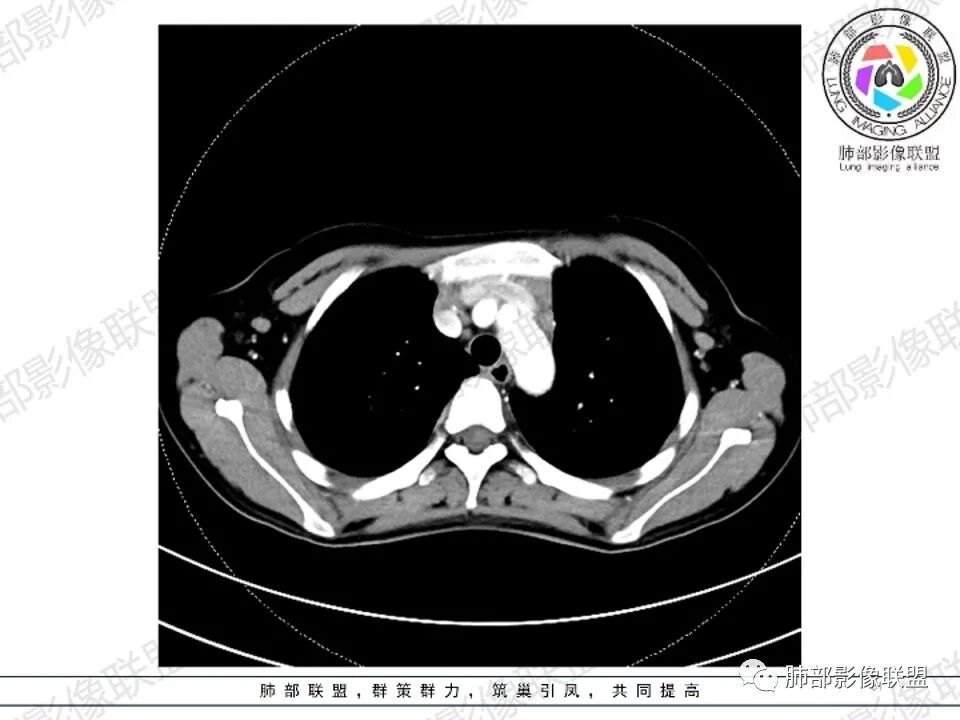

女,27,间断头晕、乏力3年,左眼视物模糊2月。贫血。胸部CT:前纵隔不规则肿块,多结节融合,边界不清,沿主动脉及肺动脉间隙生长,平扫密度欠均匀,增强扫描可见多发低密度坏死,纵隔血管供血穿行,腋窝多发大小不等淋巴结肿大。考虑恶性病变,胸腺癌?肉瘤?淋巴瘤?鉴别胸腺瘤、结节病等。

2.影像显示前纵隔不规则块状影,依势贴附心脏大血管旁,密度不均,边界不甚清楚,有结节融合感。

3.病灶轻度不均匀强化,可见血管穿行,散在液性低密度区。

双肺门未见肿大淋巴结。

4.双侧腋窝区见增大淋巴结,边界清楚。

1.年轻女性,前纵隔不规则块状影,密度不均,边界不甚清楚,有结节融合感,轻度不均匀强化,可见血管穿行,最常见最符合的无疑是淋巴瘤!